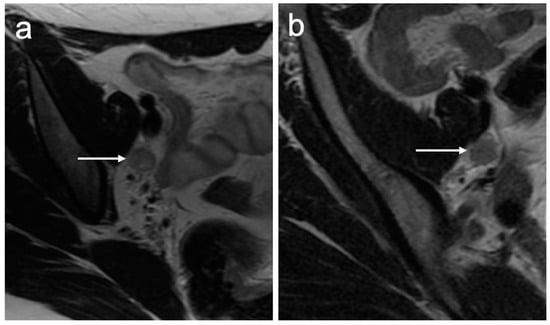

| IIB | With parametrial invasion but not up to the pelvic wall |